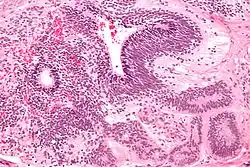

Mikroskopowo guz pęcherzyka żółtkowego prezentuje liczne odmienne wzory architektoniczne i cytologiczne[107][108]. Zwykle w obrębie jednego guza widoczne jest kilka wzorów utkania, które mogą występować w porównywalnych proporcjach, ale czasem jeden z nich może dominować[107].

- Wzór mikrotorbielkowaty (microcystic/reticular pattern)

Jest to najczęstszy wzór utkania, cechuje się występowaniem komórek z wyraźnymi wakuolami, które tworzą obraz siatki czy plastru miodu z widocznymi sznurami małych komórek i wolnych przestrzeni. Komórki nowotworowe są małe, mogą być ściśnięte przez duże wakuole, jadra komórkowe są małe[107][108].

- Wzór torbielowaty (macrocystic pattern)

W utkaniu widoczne są liczne cienkościenne przestrzenie o różnych rozmiarach[107]. Wzór wynika z połączenia mikrotorbieli[108].

- Wzór lity (solid pattern)

Lity wzór utkania budują ściśle przylegające arkusze wielobocznych komórek z wyraźną eozynofilną lub jasną cytoplazmą, wyraźnymi jednolitymi jądrami komórkowymi. Aktywność mitotyczna jest wysoka[107][108].

- Wzór gruczołowo-pęcherzykowy (glandular-alveolar pattern)

Wzór utkania składa się z nieregularnych pęcherzyków, struktur podobnych do gruczołów czy cewek wyłożonych płaskimi, sześciennymi lub wielobocznymi komórkam[107][108].

- Wzór zatoki endodremalnej (endodermal sinus pattern)

W utkaniu widoczne są struktury nazywane ciałkami Schiller-Duvala zbudowane z centralnego naczynia otoczonego luźną tkanką łączną i sześciennymi albo walcowatymi komórkami nowotworowymi z jasną cytoplazmą i wyraźnymi jądrami. Są one otoczone przez przestrzenie torbielowate wyłożone płaskim nabłonkiem[107][108]. Ciałka Schiller-Duvala są uważane za charakterystyczną cechę guza zatoki endodermalnej, ale ich nieobecność nie wyklucza rozpoznania tego nowotworu[107].

- Wzór brodawkowaty (papillary pattern)

Utkanie tworzą małe, nieregularne brodawki widoczne w przestrzeniach torbielowatych. Brodawki są złożone z rdzenia z tkanki łącznej wyłożonego komórkami nowotworowymi[107][108].

- Wzór śluzowy (myxoid pattern)

Utkanie tworzą rzadkie sznury, pasma lub pojedyncze komórki w obrębie obfitego podścieliska śluzowego[107][108].

- Wzór wielopęcherzykowy (polyvesicular vitelline pattern)

Utkanie budują pęcherzyki lub torbiele o różnym kształcie i wielkości, wyłożone spłaszczonymi lub walcowatymi komórkami, pęcherzyki są otoczone tkanką łączną o różnym stopniu komórkowości[107][108].

- Wzór wątrobiakopodobny (hepatoid pattern)

Ten wzór utkania występuje w 20% nowotworów pęcherzyka żółtkowego. W utkaniu są obecne komórki przypominające hepatocyty, z obfitą eozynofilną cytoplazmą, centralnie położonym dużym jądrem komórkowym i wyraźnym jąderkiem. Komórki są ułożone w gniazda, cewki lub beleczki[108].